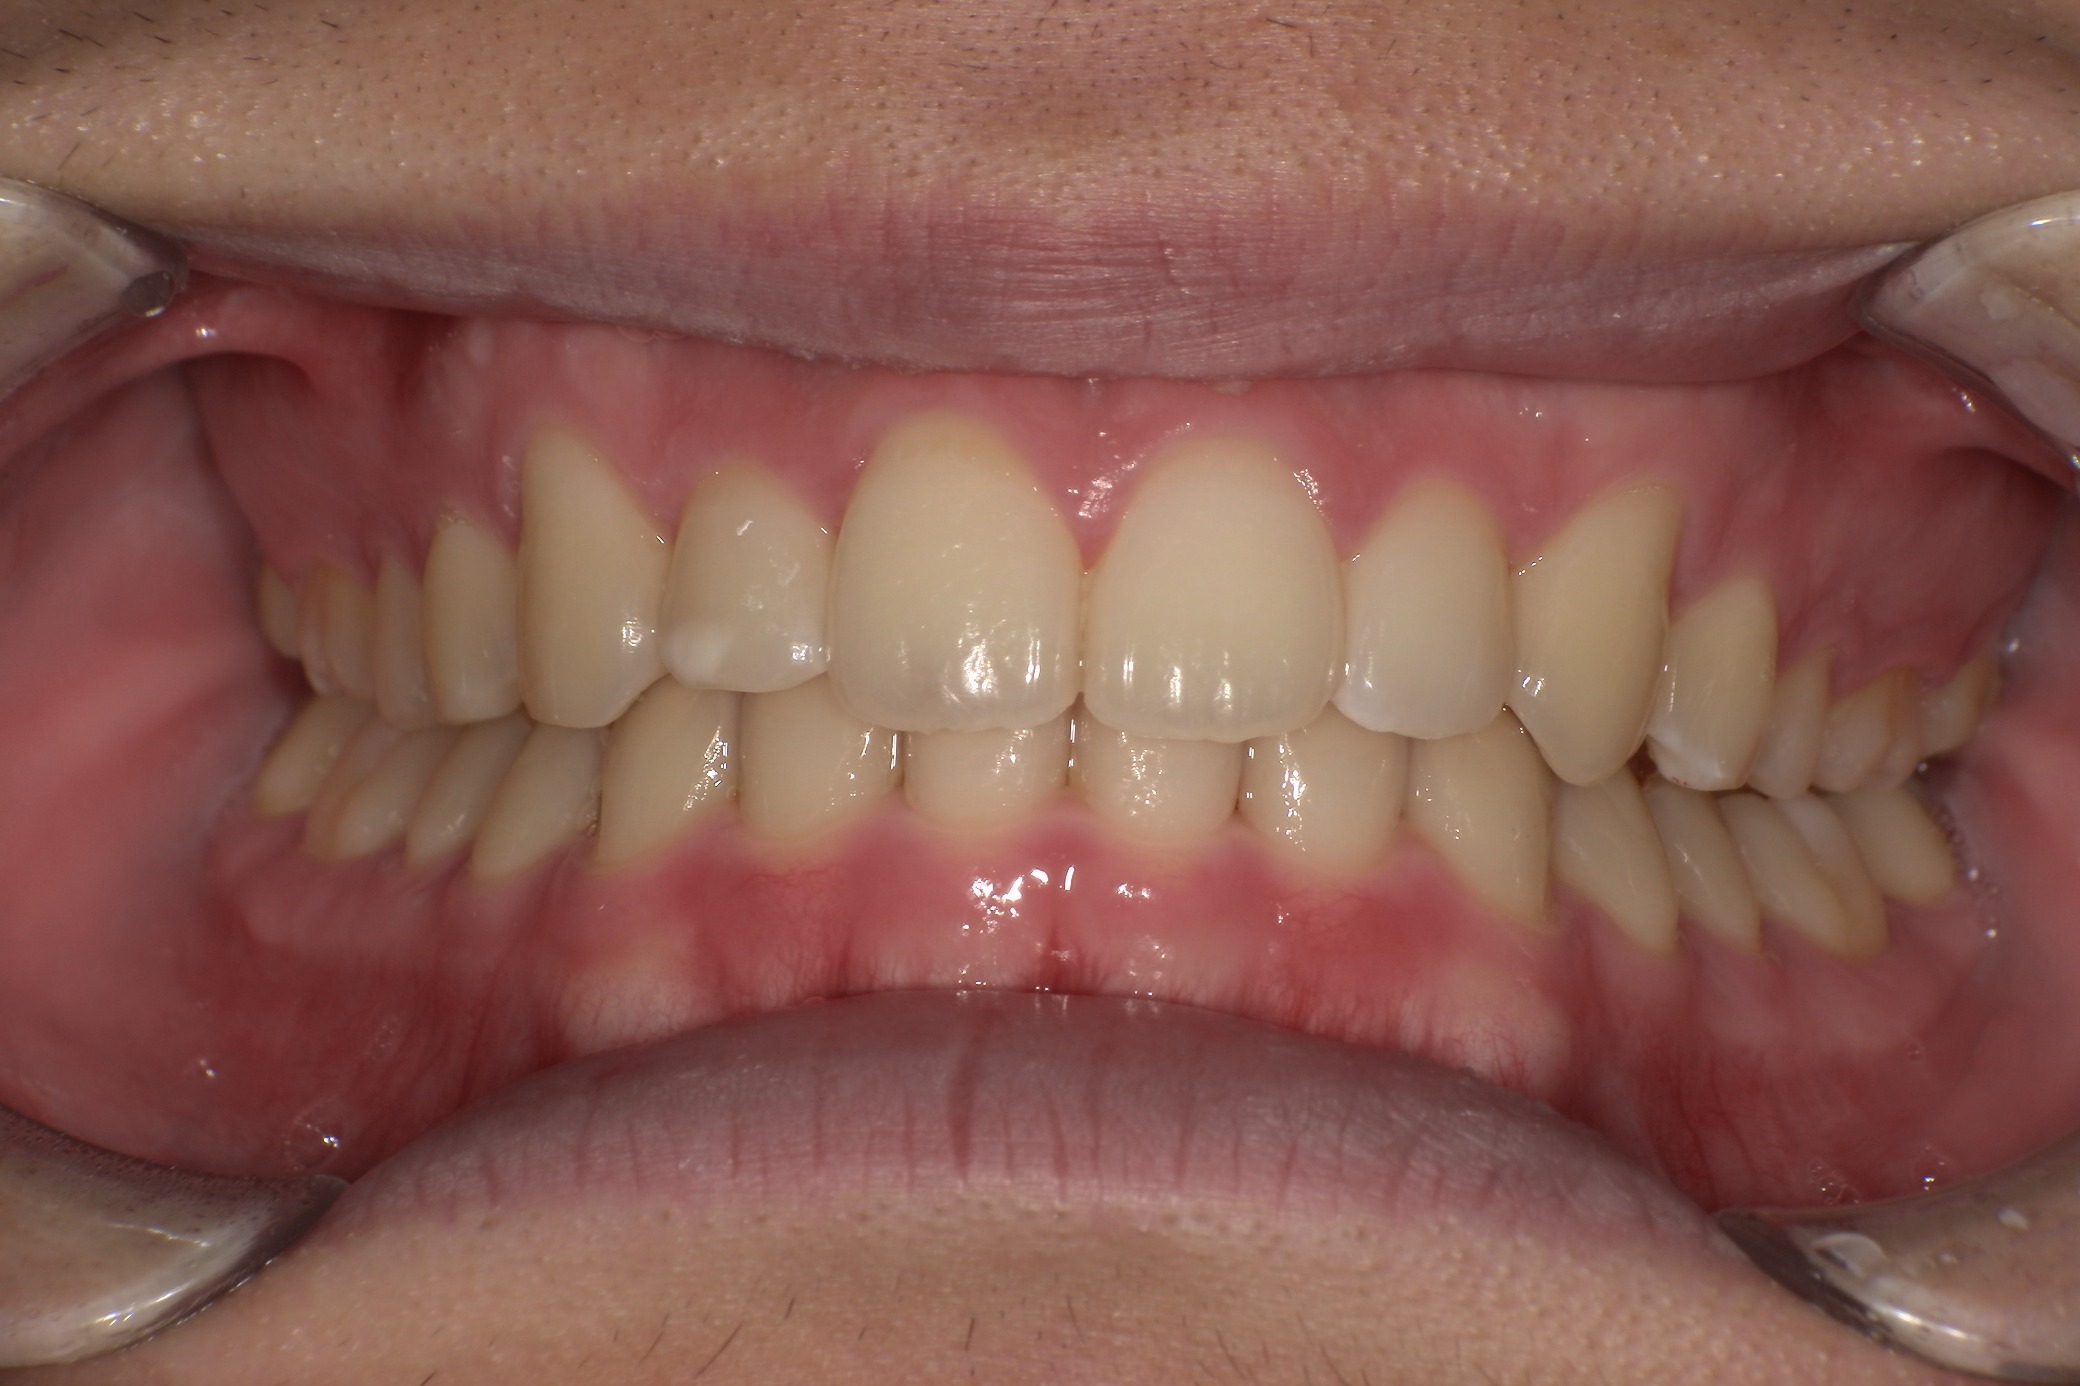

歯並びがコンプレックスで友人と写真を撮る際も気にしてしまっていたという20歳の男子大学生I.T.様にのI.T.様。始めやすい価格と目立ちにくさからスマイルモア矯正を選び、自信を持って笑えるようになった経緯を伺いました。

| 詳細情報 | |

|---|---|

| 費用 | 360,000円(税込396,000円) |

| 治療期間 | 6ヶ月 |

| 治療内容 | マウスピースを用いた歯列矯正 |

| 追加処置 | IPR |